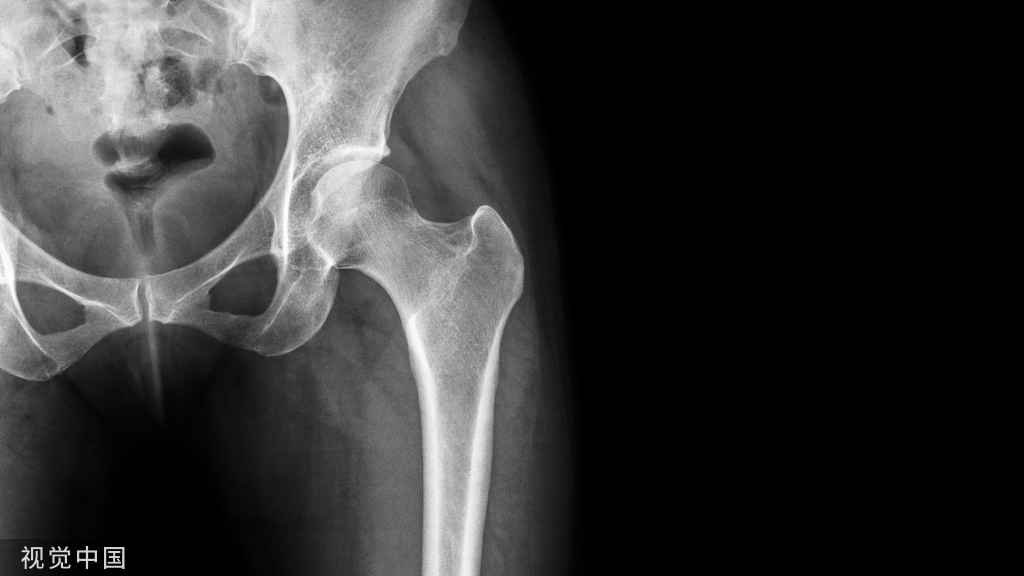

典型ONFH的MRI表现为T1WI低信号带包绕脂肪信号,T2WI出现双线征(double line sign),T2WI抑脂像或STIR序列出现片状或带状高信号(图1),此异常信号改变多数位于闭合的骨骺线以近,但部分ONFH的坏死信号带可穿透骨骺线至股骨头远端,少数可穿透股骨颈部。约20%的ONFH不出现T2WI的双线征。如在股骨头颈及转子部出现骨髓水肿,提示坏死病灶进展到围塌陷期。

图1 典型的股骨头坏死MRI图像(a)T1WI带状低信号;(b)T2WI双线征;(c)T2WI抑脂像示带状高信号